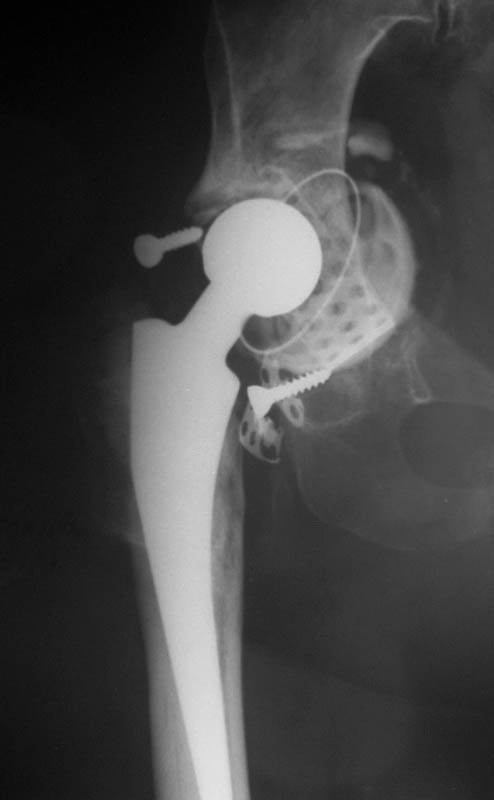

Мужчина, 38 лет. Двусторонний диспластический коксартрз, кифосколиоз.Правый сустав прооперирован 12.12.00, левый - в апреле 2003 г. Справа вывихнулась <чашка>.

Предполагается заменить <чашку>, наростив крышу <тутопластом>? Возможно ли использовать бесцементную <чашку>? Мнения? Заранее благодарю! С уважением,А.В.Владзимирский

На мой взгляд, оптимальным вариантом может быть использование антипротрузионой сетки и цементной чашки. Пластика крыши с учётом величины дефекта - любым материалом на Ваше усмотрение (ауто-, алло-)

Использовать бесцементную чашку я бы не рискнула.